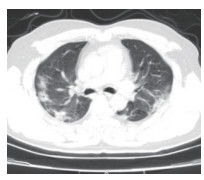

2.5 胸部CT结果入院时,为所有患者进行了胸部螺旋CT检查,47例(71.2%)患者表现为双侧多发性斑片样和磨玻璃样混浊,典型影像学表现见图 1,19例(28.8%)患者表现为单侧肺炎,典型影像学表现见图 2。

| 图 2 单肺感染 Fig 2 Single lung infection |

在入院治疗3 d后,再次对所有患者复查了胸部螺旋CT。39例(59.1%)患者肺部感染灶有不同程度增多,27例(40.9%)患者肺部感染灶无明显进展。